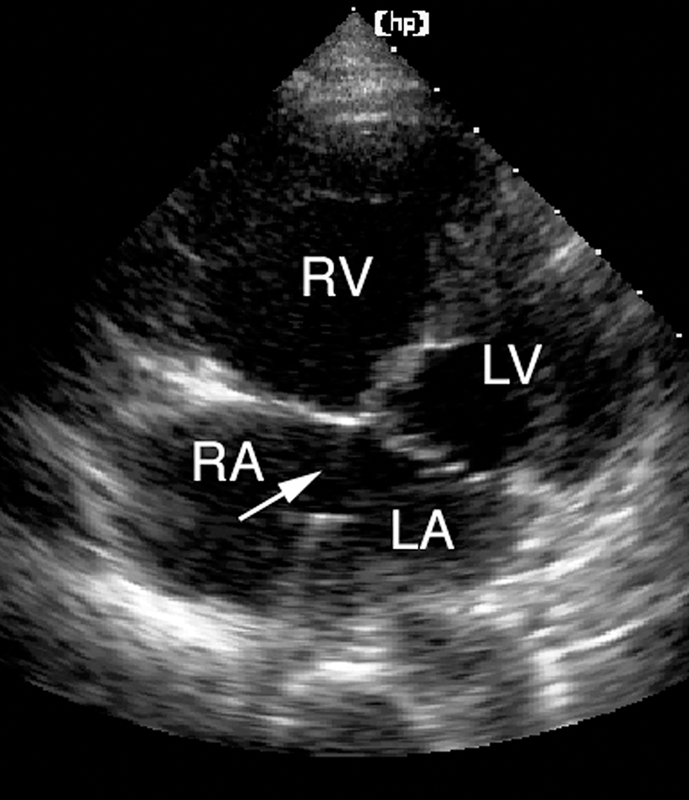

فحوصات تشخيصية لبعض امراض القلب والشرايين التاجية